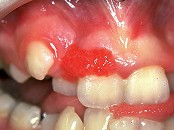

1.組圖是牙齦瘤患者,有關此病的描述不正確的是  (    )

正確答案:D